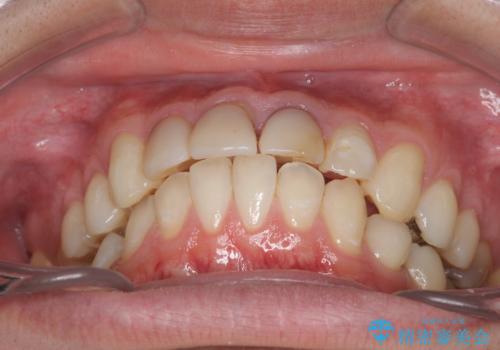

歯の挺出を行ったことで歯ぐきの腫れも改善され、安定した歯周環境下でのセラミッククラウン治療を行うことができました。

視診・X線検査・歯周組織検査より下記のような問題が列挙され、長期的な予後を見込むために一つづつ問題の解決を計ります。

・歯肉縁下カリエス →部分矯正による歯の挺出・歯周外科